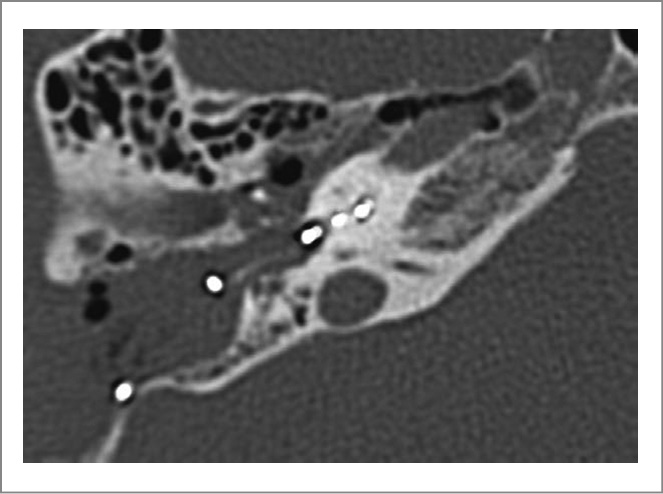

В результате оперативного вмешательства рассверлен базальной завиток улитки, однако доступ к среднему завитку выполнить не удалось. Интраоперационно принято решение о проведении КИ с использованием имплантата с коротким прямым электродом 11 мм. В ходе операции удалось ввести 10 активных электродов цепи кохлеарного имплантата из 12. Общее сопротивление зафиксировано в пределах нормы по всем электродам, что не типично для пациентов с ОУ. Несмотря на неизмененную анатомию среднего уха, акустические рефлексы стременной мышцы не получены. При проведении телеметрии нервного ответа достоверно получены ответы на 6 электродах из 12 (рис. 3).

Рис. 3. КТ правой ВК после операции с НВ активного электрода.